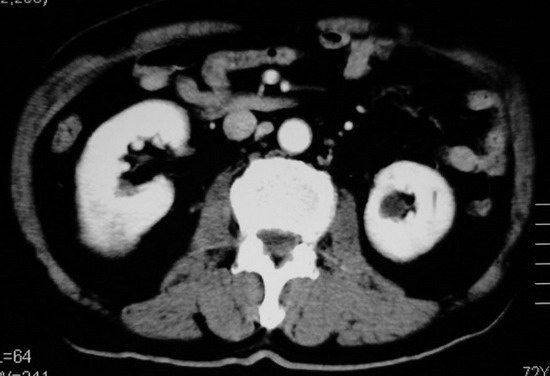

以下是引用杀毒软件在2008-11-17 19:15:00的发言:[br]考虑------右肾癌合并肾静脉---同侧肾上腺受侵可能性大

以下是引用zjzjr在2008-11-17 20:45:00的发言:[br]考虑------右肾癌合并肾静脉---同侧肾上腺受侵可能性大及腹膜后淋巴结转移.